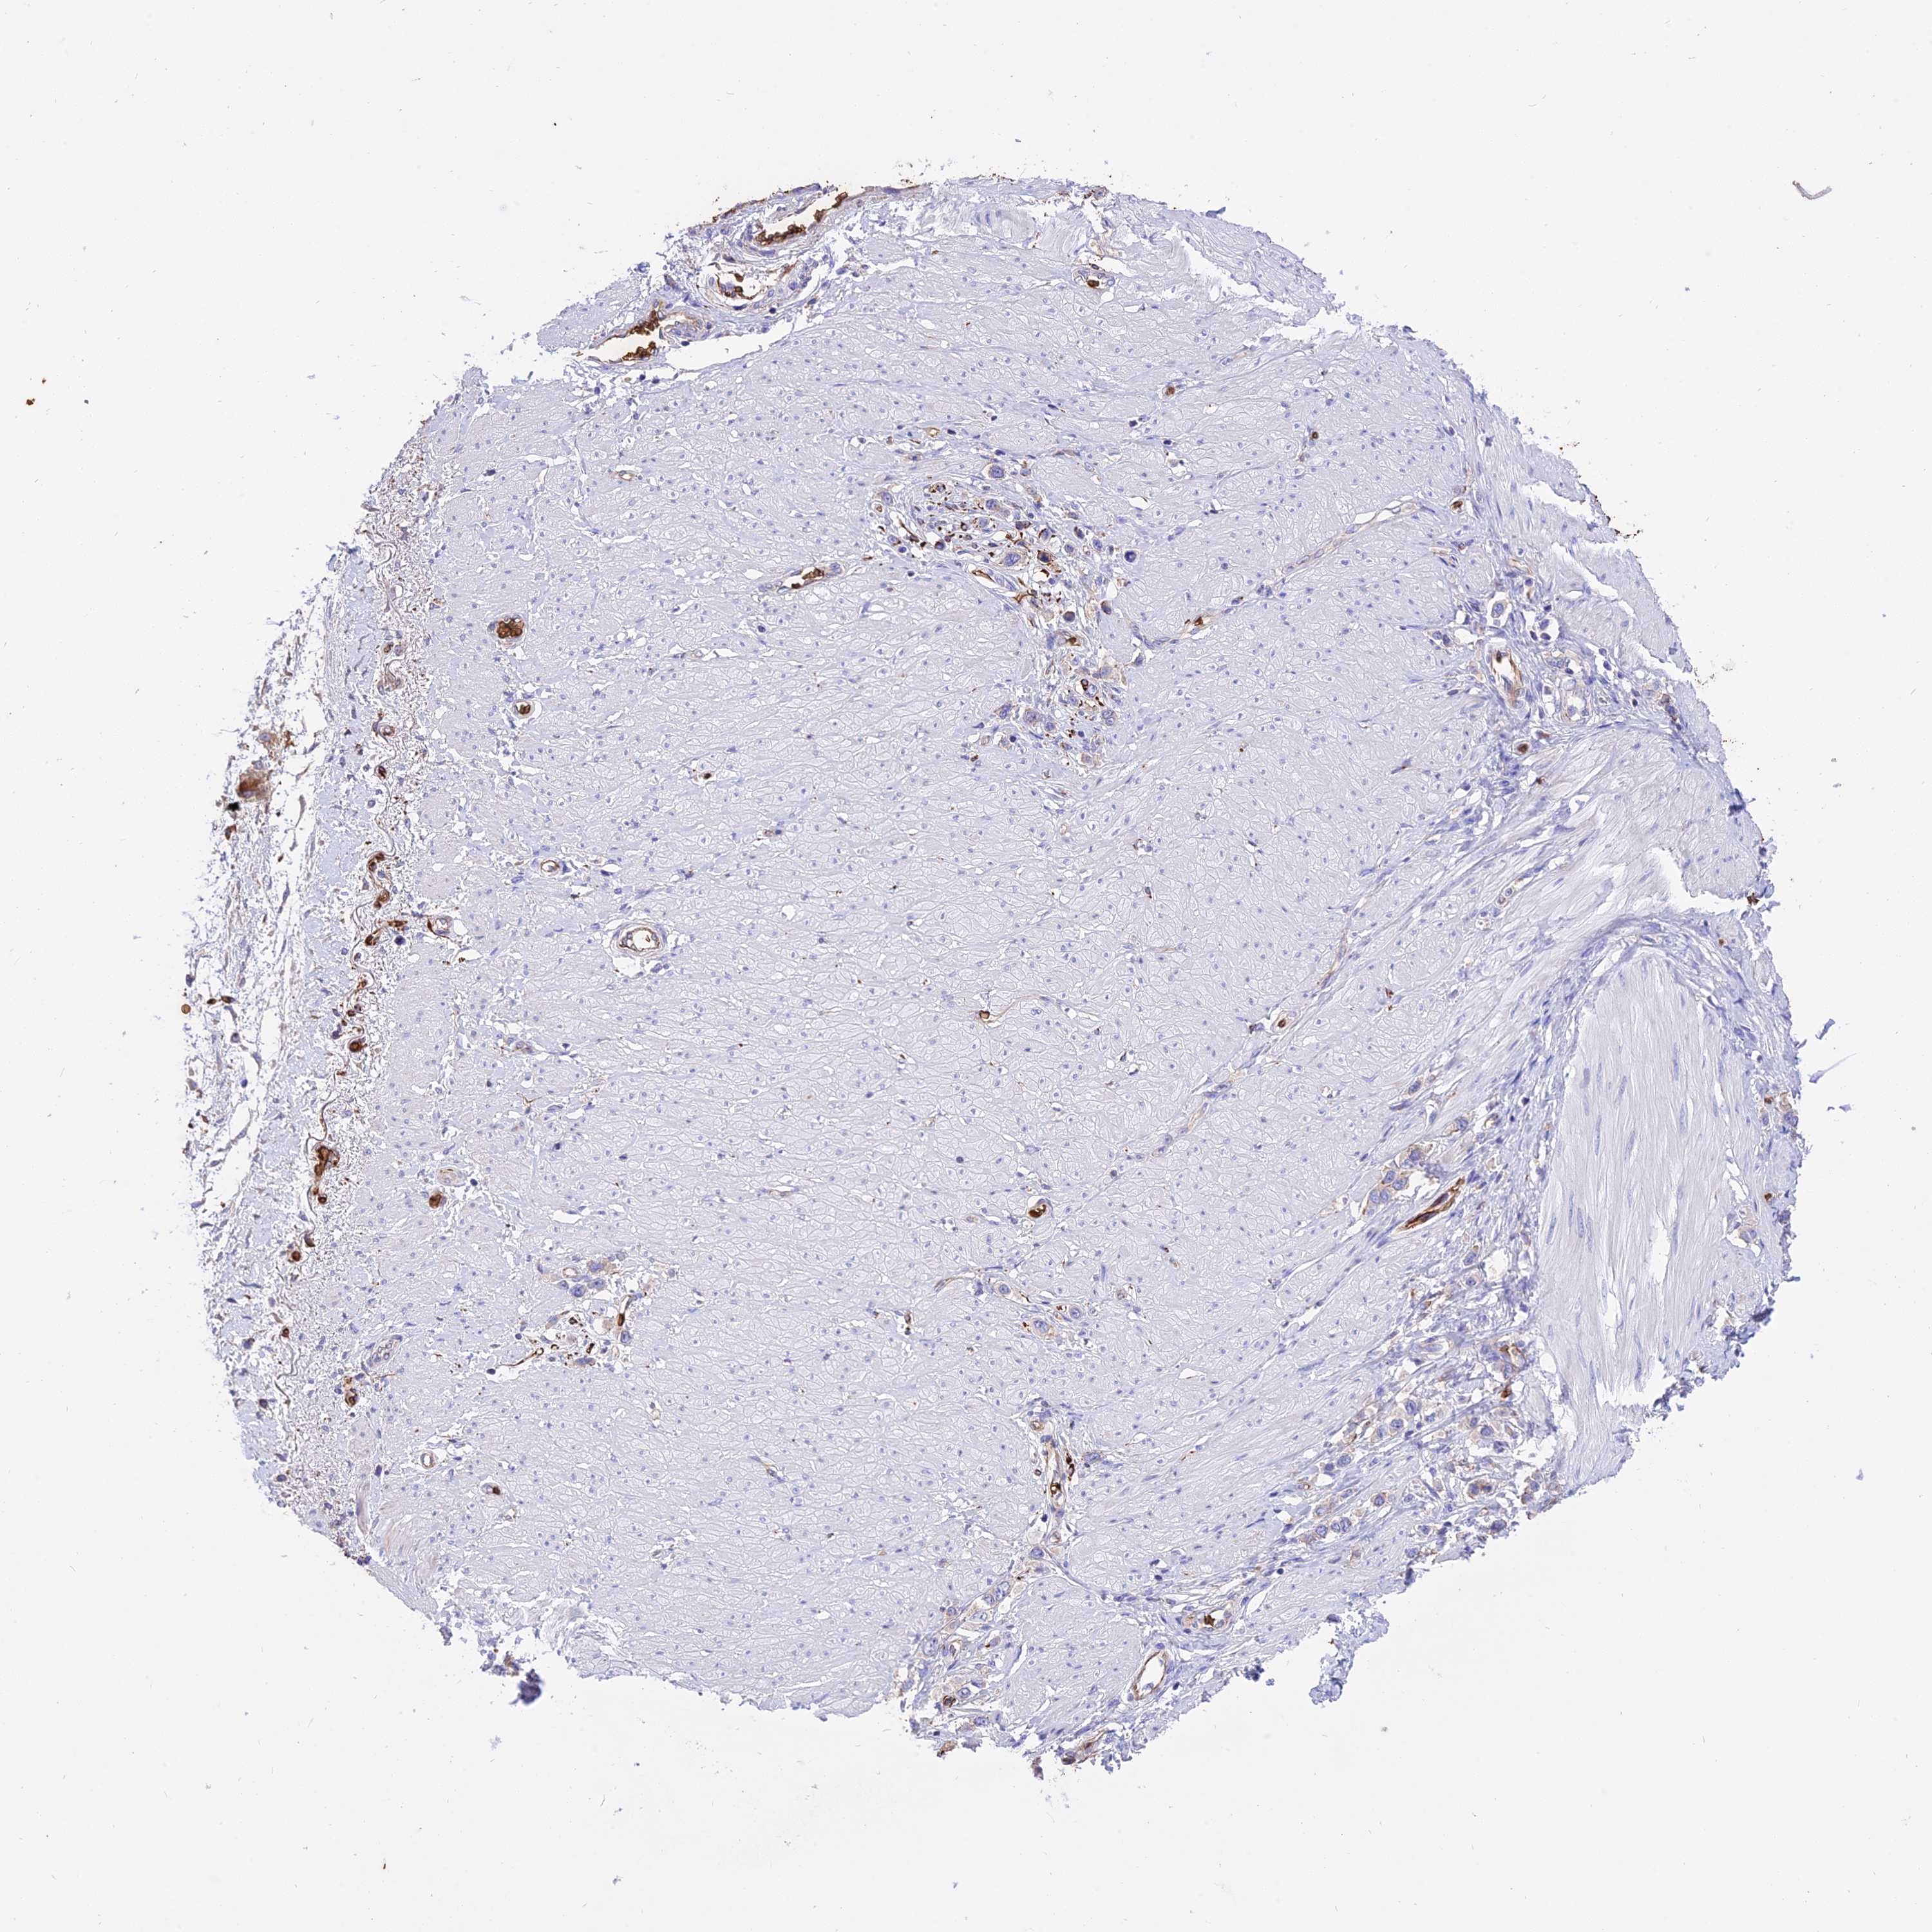

STOMACH CANCER - Protein expressioni

A mouse-over function shows sample information and annotation data. Click on an image to view it in a full screen mode. Samples can be filtered based on level of antibody staining by selecting one or several of the following categories: high, medium, low and not detected. The assay and annotation is described here.

Note that samples used for immunohistochemistry by the Human Protein Atlas do not correspond to samples in the TCGA dataset.

Antibody stainingi

Antibody staining in the annotated cell types in the current human tissue is reported as not detected, low, medium, or high, based on conventional immunohistochemistry profiling in selected tissues. This score is based on the combination of the staining intensity and fraction of stained cells.

Each image is clickable and will lead to virtual microscopy that enables deeper exploration of all samples and also displays staining intensity scores, fraction scores and subcellular localization as well as patient and tissue information for each sample.

Antibody HPA041608

Antibody HPA042459

Staining

High

Medium

Low

Not detected

Intensity

Strong

Moderate

Weak

Negative

Quantity

>75%

75%-25%

<25%

None

Location

Nuclear

Cytoplasmic/membranous

Cytoplasmic/membranous,nuclear

Adenocarcinoma, NOS